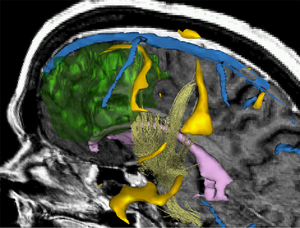

3D Rendering showing a combination of morphology, fMRI and DTI. This type of visualization can be used to support surgical decisions. Talos et al. MICCAI'03

Surgery today relies conceptually on the same principles as it did three thousand years ago: the surgeons use their hands to directly control instruments and they use their eyes to provide them with feedback about the effect of their manipulations. Accordingly, a surgeon needs access to the site of an operation for both reasons: visualization and mechanical access.